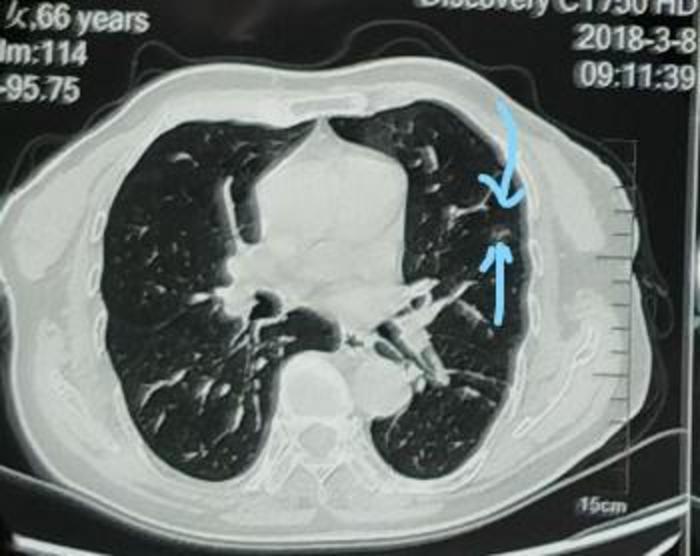

我对左下方混合磨玻璃结节外侧的一小块磨玻璃成分进行了CT值测量,发现其CT值是-165,因为其CT值是负的,不是正的,证实结节的外侧边缘有磨玻璃成分,所以这个结节一实性成分为主、磨玻璃成分为辅,是一个大型混合磨玻璃结节。即使不就行肺穿刺检查,也有95%的把握这个结节是恶性的肺癌,而且应该已经到了浸润性腺癌阶段。

上图是今年住院后左下肺癌的PET,可见结节的代谢稍增高,看起来局部发红一些。

上图是今年住院后左上肺结节的PET,可见结节的代谢正常,看起来与周围组织颜色一样,PET 考虑这个结节是慢性炎症。